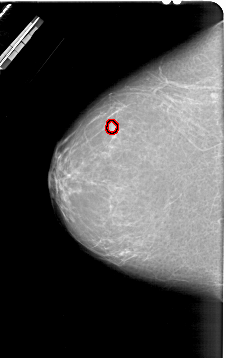

FILE: A_1830_1.LEFT_MLO.OVERLAY

TOTAL_ABNORMALITIES 1

ABNORMALITY 1

LESION_TYPE MASS SHAPE OVAL MARGINS ILL_DEFINED

ASSESSMENT 4

SUBTLETY 2

PATHOLOGY BENIGN

TOTAL_OUTLINES 1

BOUNDARY